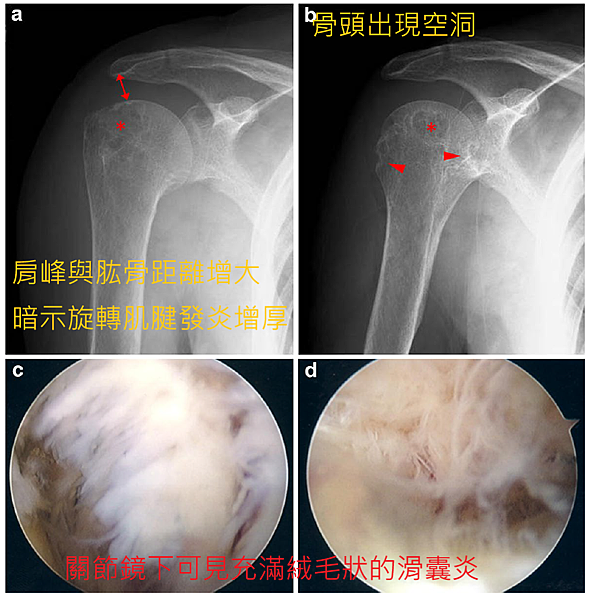

透析肩是一種類澱粉沈積的疾病,在洗腎超過十年的患者,有超過一半的病患在肩關節可以見到類澱粉沈積。其肩膀疼痛特別會出現在洗腎時,或是夜晚睡覺時,病患坐起來或站起來後症狀會緩解。在核磁共振下,可以見到旋轉肌袖及關節囊增厚,有積水在肩盂關節及肩峰下滑囊,在靠近關節面的肱骨頭會有囊腫。旋轉肌袖增厚是很典型的核磁共振表現,正常旋轉肌袖韌帶厚度約6-8mm,透析肩患者有時韌帶會厚到超過一公分,大而無用的韌帶其實是因為類澱粉沉積反覆發炎所致。

保守治療可於關節內注射類固醇,積極治療使用微創肩關節鏡將所有發炎組織切除,可以達到九成以上的成功率。建議須早期治療,因為如果導致骨骼結構變形,使用微創關節鏡治療就可能不會很理想。